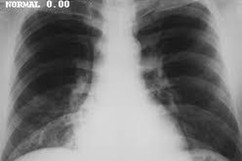

DiagnoSmart is a groundbreaking system designed for early disease identification. Utilizing state-of-the-art deep learning algorithms, the platform focuses on predicting the patient's condition for four specific diseases through image processing. In cases where image processing is not feasible, DiagnoSmart seamlessly integrates machine learning algorithms to ensure a versatile diagnostic approach. To enhance user experience, the platform incorporates a chatbot functionality, powered by Kore.ai XO Platform, guiding users through making appointments with doctors and providing preliminary diagnosis.